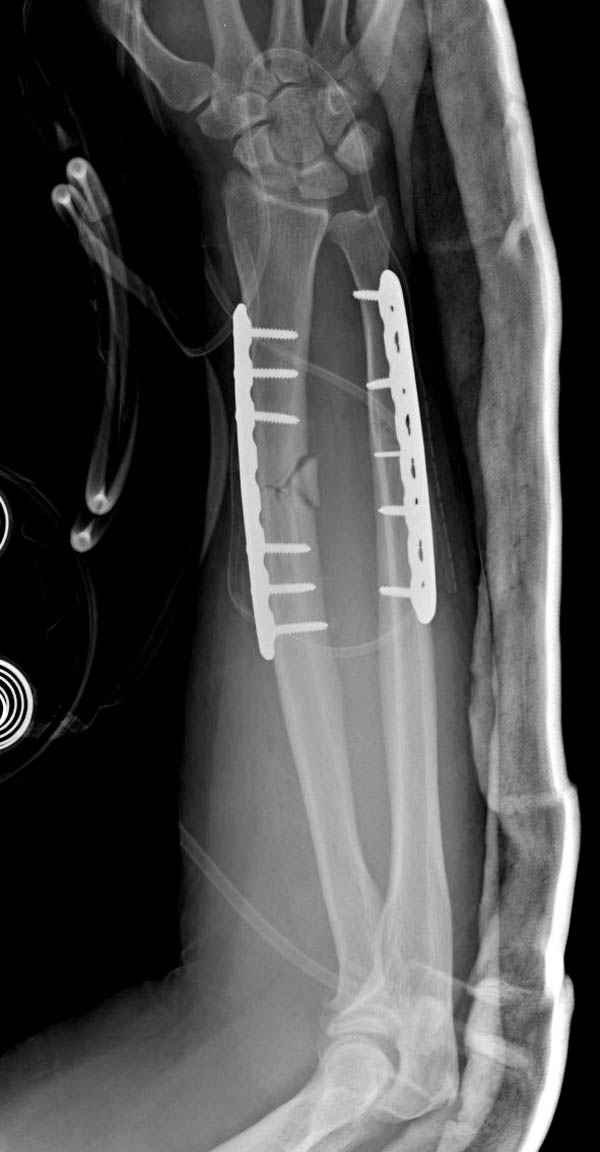

Наш недавний случай перкутанной фиксации "методом

Сиэтла" спицами 2.8 мм с резьбой на конце.

Второй случай, для лечения перелома проксимального

плеча применили пластину "Hand Innovation"

http://www.handinnovations.com/pdf/S3_technique.pdf

Пластина имеет преимущества перед другими "Locking

Implants", потому что пластину можно уложить намного ниже чем другие пластины и имеется возможности проведения шурупов под 130 градусным углом, таким образом можно уменьшить операционный разрез в проксимальной части.

Кроме перелома плеча у больного старый дистракционный перелом T12-L1 оперированный когда-то и кем-то, открытый перелом костей предплечья, который был прооперирован в ночь поступления, после I&D (хирургической обработки). Из-за разрыва селезенки при поступлении травма хирургами произведено удаление.